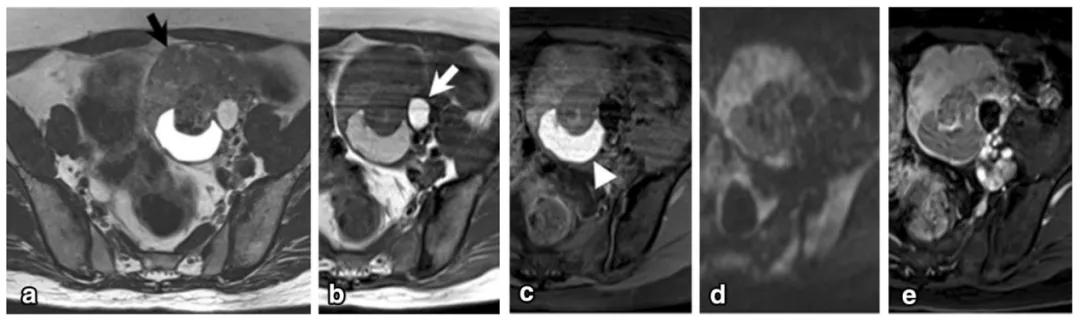

女,50 岁,卵巢类癌与成熟畸胎瘤及卵巢甲状腺肿。左卵巢囊实性肿物,实性成分 T2WI 呈低信号(图 a 黑箭),T1WI 呈稍低信号(图 b),T1WI 压脂呈稍高信号(图 c),DWI 呈高信号(图 d),增强扫描明显强化(图 e)。肿物内囊性成分 T1WI 呈高信号(白箭头)。肿物并存成熟畸胎瘤(白箭)